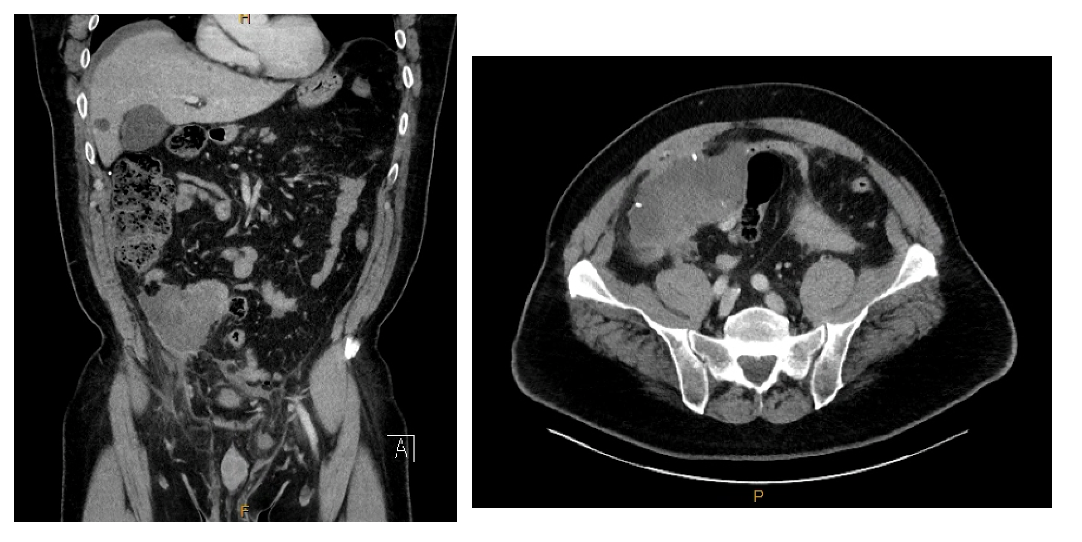

CT demonstrating large complex fluid vs mass (11.7 x 6.2 cm) in the right lower quadrant ileocolic mesentery